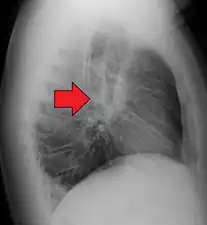

Hilar adenopathy especially on the person's left (AP CXR)

Hilar adenopathy especially on the person's left (lateral CXR)

Hilar adenopathy especially on the person's left (coronal CT)

Hilar adenopathy especially on the person's left (transverse CT)